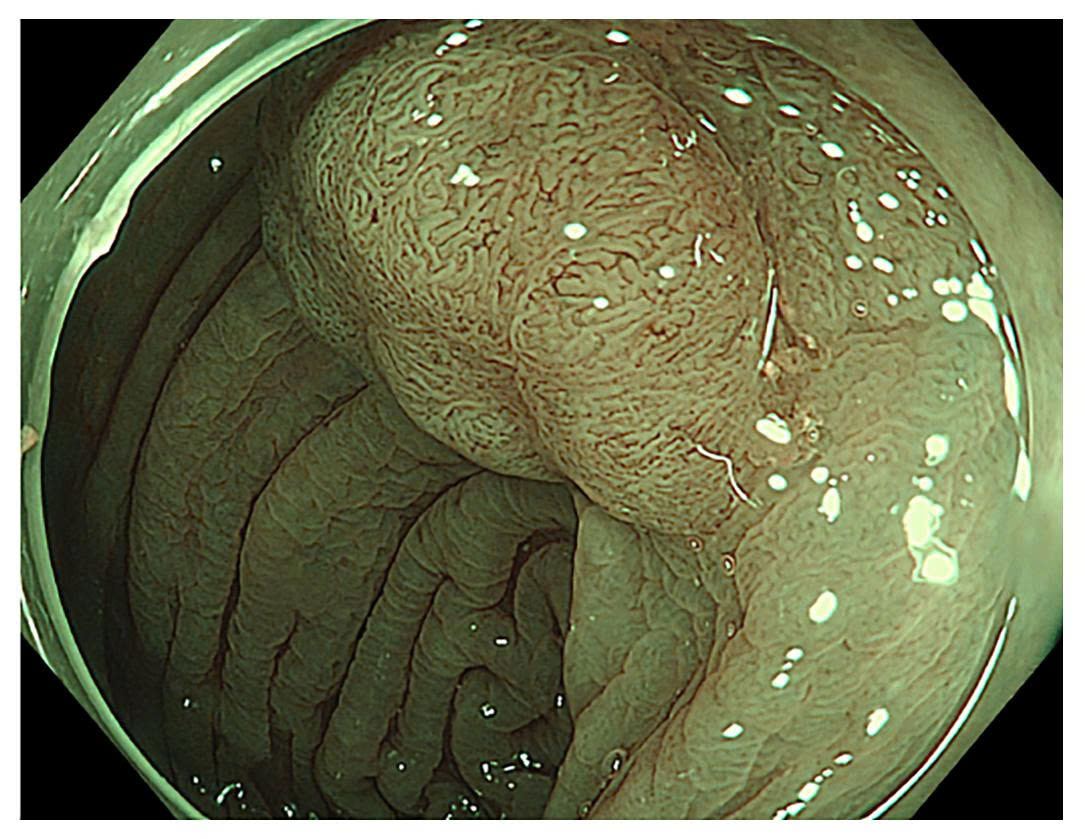

Bệnh nhân V.T.H (75 tuổi, địa chỉ Cam Ranh – Khánh Hòa) hay bị đau bụng, rối loạn đại tiện. Cách đây hơn 1 tháng, bệnh nhân đến Bệnh viện 22-12 khám và nội soi phát hiện polyp lớn ở đại tràng Sigma kích thước #25mm, dạng dẹt, chân rộng, phân loại JNET 2A. Kết quả giải phẫu bệnh nghịch sản tuyến đại tràng – một dạng tổn thương tiền ung thư, nếu không điều trị sớm, nguy cơ biến chứng rất cao.

Bệnh nhân được tư vấn điều trị bằng phương pháp nội soi cắt dưới niêm mạc ESD để loại bỏ toàn bộ polyp lớn mà không cần phẫu thuật mở bụng. Đây là phương pháp tiên tiến cho phép cắt trọn tổn thương trong một khối – giảm thiểu nguy cơ sót tế bào ung thư và giữ nguyên cấu trúc đại tràng.